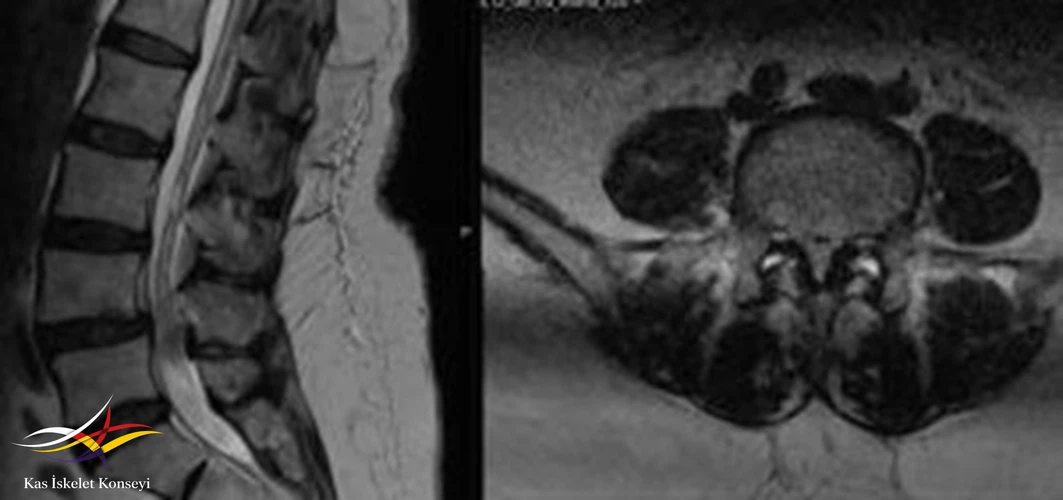

İncelemeler: Lomber MRG'de L4-5 seviyesinde dejeneratif listezise bağlı daralma mevcut.

Resim 1. Lomber MRG'de L4-5 seviyesinde faset eklemlerde ayrışma, ligamentum flavum kalınlaşmasıyla seyreden grade 1 spondilolistezis ve buna sekonder kanal darlığı görülmekte.